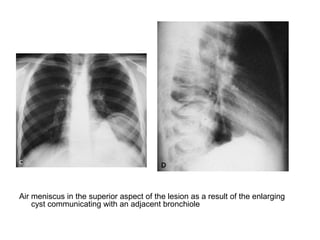

Air meniscus in the superior aspect of the lesion as a result of the enlarging

cyst communicating with an adjacent bronchiole

Water Lilly